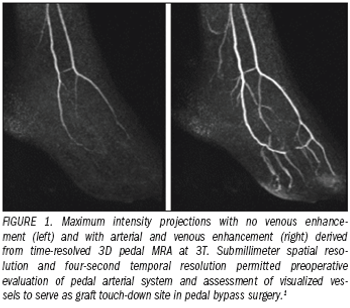

Cardiovascular MR imaging has become a valuable diagnostic modality.

Cardiovascular MR (CVMR) imaging has become a valuable diagnostic modality.